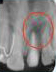

After 3 months

x-ray post operation